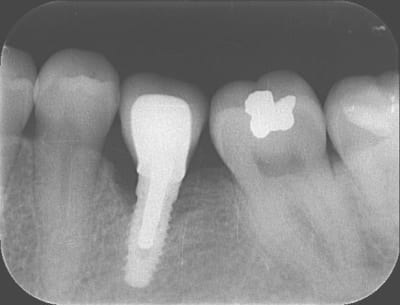

Voici trois Rx : cratère ou pas ? quel taux d'échec à 5 ans (tout les implants), ce sont les mêmes : 3I plateforme plate, deux temps chir, pas de plateform switching, pilier vissé prothèse scellée, 3 mois d'OI.

Crat 1 k8pnfh - Eugenol

Crat 2 ra8vyw - Eugenol

Crat 3 hpsffn - Eugenol